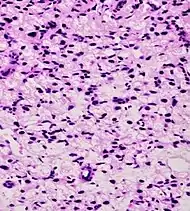

Foamy gland carcinoma 17%[5][notes 1]13–23%[5][notes 1]

• Abundant foamy cytoplasm[1]

• Nuclei may be small and pyknotic - benign-looking[1]

• Infiltrative pattern

• Foamy cells:

• PSA+ and CD68− [1]

• AMACR+ in 68% of cases[1]

Based on architecture, discounting foamy cytoplasms[1]